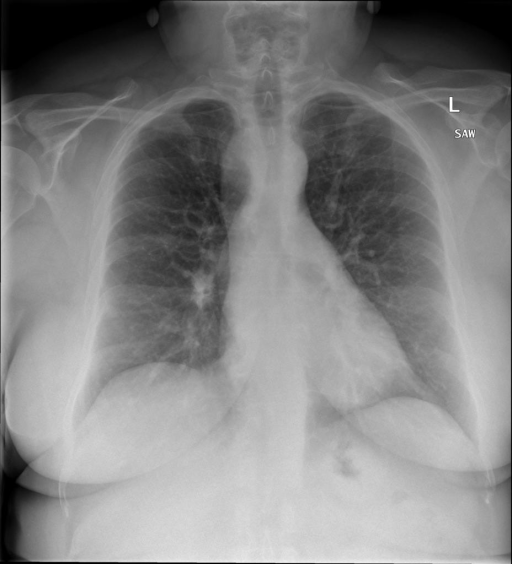

# 本文贡献 ![](./assets/images/xrayglm.png) - 借助ChatGPT以及公开的数据集,我们构造了一个`X光影像-诊断报告`对的医学多模态数据集; - 我们将构建的中文胸部X光片诊断数据集在[VisualGLM-6B](https://github.com/THUDM/VisualGLM-6B)进行微调训练,并开放了部分训练权重用于学术研究; # 数据集 - [MIMIC-CXR](https://physionet.org/content/mimic-cxr-jpg/2.0.0/)是一个公开可用的胸部X光片数据集,包括377,110张图像和227,827个相关报告。 - [OpenI](https://openi.nlm.nih.gov/faq#collection)是一个来自印第安纳大学医院的胸部X光片数据集,包括6,459张图像和3,955个报告。 在上述工作中,报告信息都为非结构化的,不利于科学研究。为了生成合理的医学报告,我们对两个数据集进行了预处理,并最终得到了可以用于训练的**英文报告**。除此之外,为了更好的支持中文社区发展,借助ChatGPT的能力,我们将英文报告进行了中文翻译,并最终形成了可用于训练的数据集。 |数据集|数量|下载链接| |:-|:-|:-| |MIMIC-CXR-zh|-|-| |OpenI-zh|6,423|[诊疗报告](./data/Xray/openi-zh.json) 、[X光影像](https://pan.baidu.com/s/13GBsDMKf6xBZBSHpoWH_EA?pwd=k9sh)| # 快速上手 1. 安装环境 ```bash # 安装依赖 pip install -r requirements.txt # 国内换源安装依赖 pip install -i https://mirrors.aliyun.com/pypi/simple/ -r requirements.txt ``` 此时默认会安装`deepspeed`库(支持`sat`库训练),此库对于模型推理并非必要,同时部分`Windows`环境安装此库时会遇到问题。 如果想绕过`deepspeed`安装,我们可以将命令改为: ```bash # 安装依赖 pip install -i https://mirrors.aliyun.com/pypi/simple/ -r requirements_wo_ds.txt # 安装SwissArmyTransformer pip install -i https://mirrors.aliyun.com/pypi/simple/ --no-deps "SwissArmyTransformer>=0.3.6" ``` 2. 模型推理 CLI推理: ```python python cli_demo.py --from_pretrained checkpoints/finetune-XrayGLM-05-25-01-04 --prompt_zh '详细描述这张胸部X光片的诊断结果' ``` 更多[参数](https://github.com/WangRongsheng/XrayGLM/blob/main/cli_demo.py#L16) # 效果展示 诊断: |X光影像|诊疗报告(医生)|XrayGLM| |:-|:-|:-| |![](./data/Xray/2_1.png)|根据X射线图像,心脏大小正常,肺部看起来很清晰。已经排除了肺炎、积液、水肿、气胸、腺病、结节或肿块的存在。该发现表明一切正常。换句话说,总体印象是胸部正常。|X光片显示,心脏大小正常。肺部没有气胸或胸腔积液的证据。骨骼结构看起来没有任何异常。总的来说,X光片表明没有发现急性心肺疾病的迹象。| |![](./data/Xray/2882_1.png)|X光图片显示没有扭曲的区域、可疑的骨质不透明度或胸腺积液。心脏大小轻微增大,但非常稳定。此外,没有气胸的证据,肺野也正常。总体来说,X光片显示没有急性心脏异常,但要注意轻微的心脏扩大。|X光片显示,心脏大小正常。肺部和纵隔轮廓清晰,没有气胸或胸腔积液的证据。骨骼结构完整,没有任何急性异常。| |![](./data/Xray/2577_1.png)|心影形态在正常范围内。没有急性骨质异常。有可能出现没有明显的吸水或肺实质状况的线索。没有大面积积液或气胸。有可能怀疑其有误吸或肺实质问题。为了确诊和治疗,可能需要进行适当的影像学随访。|心脏大小正常,肺部和纵隔轮廓清晰。没有急性异常或活动受限的证据。没有任何明显的气胸、胸腔积液或肺不张的迹象。此外,也没有发现任何局灶性骨质异常或其他急性疾病。| 多轮对话: |X光影像|诊疗报告(医生)| |:-|:-| |![](./data/Xray/861_1.png)|右侧主动脉突出观察到。心脏大小正常。胸部未发现明显的肺气肿、胸膜积液或可疑的肺部病变。报告指出已知右侧主动脉情况正常。| ```bash >> X光影像路径:./data/Xray/861_1.png >> 用户:这是一张什么图? >> XrayGLM:这张图片显示的是一张肺部检查的X光片。 >> 用户:请描述这张胸部X光片的诊断结果 >> XrayGLM:心脏大小正常,肺部清晰。没有急性心肺疾病的证据。 >> 用户:是否存在肺气肿? >> XrayGLM:没有肺气肿。心脏大小正常,肺部清晰。没有发现急性心肺疾病的证据。 >> 用户:平时饮食该注意什么? >> XrayGLM:饮食应该健康,均衡。建议增加蛋白质的摄入量,因为蛋白质有助于维持肌肉和骨骼的健康。多食用蔬菜、水果、全谷物以及健康的脂肪来源如橄榄油、鱼类等可以帮助获得足够的维生素和矿物质。此外,避免过度饮酒或吸烟,这些习惯可能会对心脏健康产生负面影响。 ``` # 项目致谢 1. [VisualGLM-6B](https://github.com/THUDM/VisualGLM-6B)为我们提供了基础的代码参考和实现; 2. [MiniGPT-4](https://github.com/Vision-CAIR/MiniGPT-4)为我们这个项目提供了研发思路; 3. ChatGPT生成了高质量的中文版X光检查报告以支持XrayGLM训练; 4. [gpt_academic](https://github.com/binary-husky/gpt_academic)为文档翻译提供了多线程加速; 5. [MedCLIP](https://github.com/RyanWangZf/MedCLIP) 、[BLIP2](https://huggingface.co/docs/transformers/main/model_doc/blip-2) 、[XrayGPT](https://github.com/mbzuai-oryx/XrayGPT) 等工作也有重大的参考意义; ![](./assets/images/mpu.png) 这项工作由[澳门理工大学应用科学学院](https://www.mpu.edu.mo/esca/zh/index.php)硕士生[王荣胜](https://github.com/WangRongsheng) 、[段耀菲](https://github.com/IsBaSO4) 、[李俊蓉](https://github.com/lijunrong0815)完成,指导老师为檀韬副教授、[彭祥佑](http://www.patrickpang.net/)老师。 *特别鸣谢:[USTC-PhD Yongle Luo](https://github.com/kaixindelele) 提供了有3000美金的OpenAI账号,帮助我们完成大量的X光报告翻译工作 # 免责声明 本项目相关资源仅供学术研究之用,严禁用于商业用途。使用涉及第三方代码的部分时,请严格遵循相应的开源协议。模型生成的内容受模型计算、随机性和量化精度损失等因素影响,本项目无法对其准确性作出保证。即使本项目模型输出符合医学事实,也不能被用作实际医学诊断的依据。对于模型输出的任何内容,本项目不承担任何法律责任,亦不对因使用相关资源和输出结果而可能产生的任何损失承担责任。 # 项目引用 如果你使用了本项目的模型,数据或者代码,请声明引用: ```bash @misc{wang2023XrayGLM, title={XrayGLM: The first Chinese Medical Multimodal Model that Chest Radiographs Summarization}, author={Rongsheng Wang, Yaofei Duan, Junrong Li, Patrick Pang and Tao Tan}, year={2023}, publisher = {GitHub}, journal = {GitHub repository}, howpublished = {\url{https://github.com/WangRongsheng/XrayGLM}}, } ``` # 使用许可 此存储库遵循[CC BY-NC-SA](https://creativecommons.org/licenses/by-nc-sa/4.0/) ,请参阅许可条款。